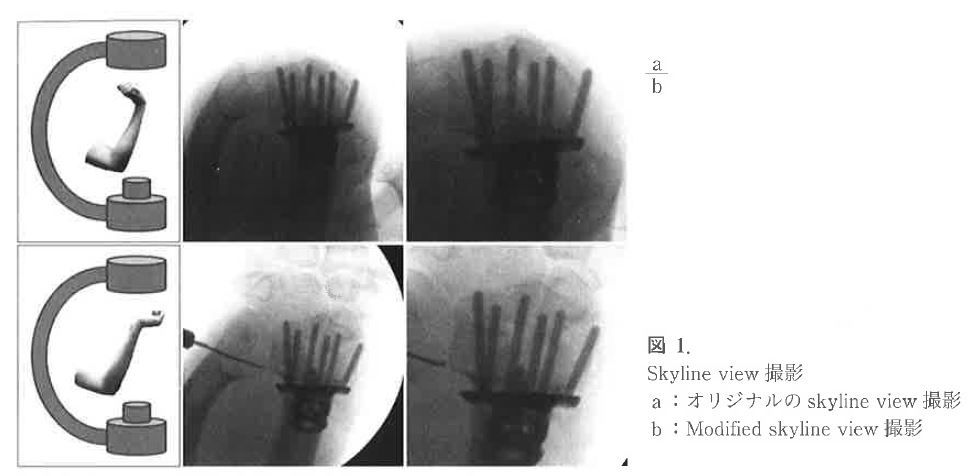

これを回避するためには2012年にJ Hand Surg EurでRiddickらが報告した、術中のSkyline viewが有用です。これは手関節屈曲70度にして接線方向から撮影する方法です。

この論文によると、Riddickらが橈骨の背側皮質と考えていたラインは、実は月状骨背側骨皮質のラインであり、実際の橈骨背側骨皮質のラインはより掌側であったそうです。

これを回避するためには、石井先生らは手関節伸展70度にして接線方向から撮影する方法(modified skyline view)の有用性を提唱されました。

上記がmodified skyline viewです。実際にみると、手根骨が重なってやや見にくいですが、オリジナルよりも正確に橈骨遠位端背側皮質とスクリュー先端の距離を判断できます。